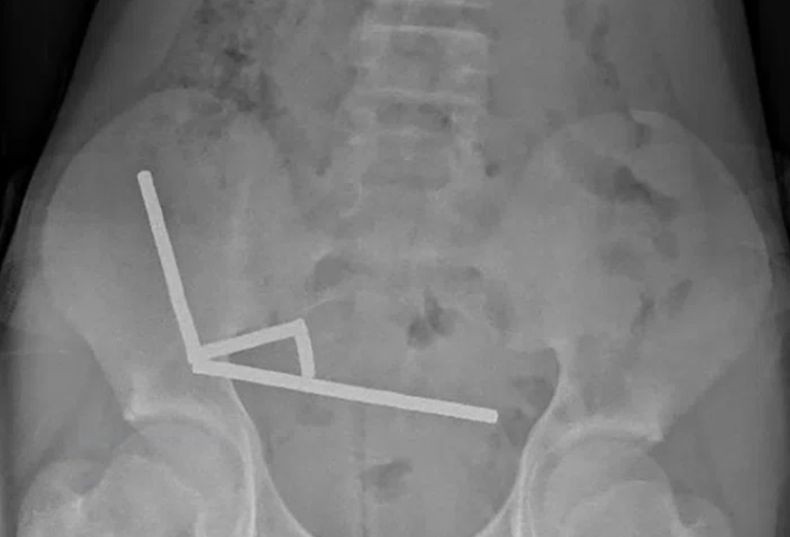

Seorang bocah 13 tahun di Selandia Baru nekat menelan 100 magnet berdaya tinggi atau neodymium (Foto: Handout)

Sementara itu hasil rontgen menunjukkan, magnet-magnet tersebut menggumpal menjadi empat garis lurus di dalam usus anak tersebut.

“Magnet-magnet ini tampaknya berada di bagian usus terpisah yang saling menempel karena gaya magnet,” kata dokter.

Para dokter mengatakan, tekanan magnet menyebabkan nekrosis atau kematian jaringan di empat area usus halus dan sekum, bagian dari usus besar pasien.